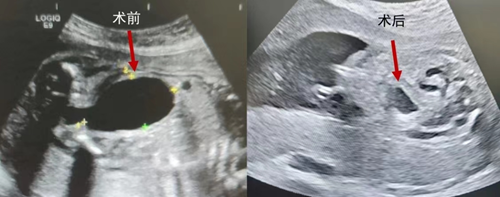

“手術(shù)利用引導(dǎo)裝置在胎兒下腹部將引流管植入胎兒膀胱內(nèi),使尿液持續(xù)引流到羊膜腔中,從而達(dá)到緩解胎兒腎臟受壓和羊水過少的目的。該手術(shù)對子宮創(chuàng)傷小,能有效的進(jìn)行膀胱內(nèi)減壓,改善胎兒宮內(nèi)情況,延長孕周,從而改善胎兒的遠(yuǎn)期預(yù)后。但由于手術(shù)對胎兒體位及穿刺部位要求極高,既要避免傷及腹腔血管和臟器,又要防止后期膀胱回縮后引流管脫落,屬于超高難度的手術(shù)?!碑a(chǎn)科中心許茜主任介紹道。

手術(shù)當(dāng)天,團(tuán)隊先通過羊膜腔內(nèi)羊水灌注增加胎兒活動的空間,以期獲得良好的胎兒穿刺體位。術(shù)中,當(dāng)引流管植入胎兒膀胱內(nèi),胎兒膀胱尿液即刻成功引流入羊膜腔,雙側(cè)泌尿系統(tǒng)積水情況明顯緩解。歷經(jīng)5個小時,手術(shù)成功完成。術(shù)后,孕媽媽和胎兒恢復(fù)良好,已順利出院。日后,將繼續(xù)在胎兒醫(yī)學(xué)門診密切隨診。